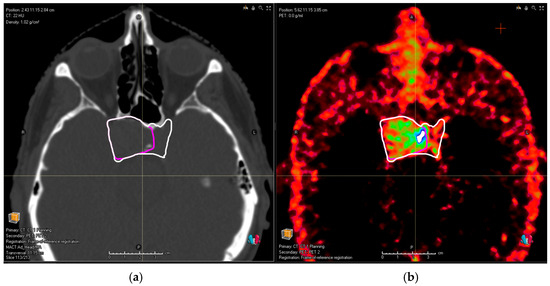

• Extensive bone infiltration in the frontobasis area from a case of an aggressive PitNET (as depicted in Figure 2).

Figure 2. Planning CT image (a) of a patient with an aggressive pituitary adenoma. Red contour shows the common MRI volume of all observers; (b) the addition of PET/CT revealed further bone infiltration into frontobasis (difficult to identify based on structural imaging alone as the patient had co-existing osteoporosis)—the gray contour representing common PET/CT and MRI volume takes this finding into account.

In all these cases, the new tumor volume first identified with the aid of DOTA PET/CT should be considered relevant for the proton treatment plan. There was no relevant tumor volume missed by observers in MRI compared to PET/CT for glomus tumors. Figure 1a shows the planning CT image of a patient with pituitary adenoma; Figure 2a shows the planning CT image of a patient with an aggressive pituitary adenoma.